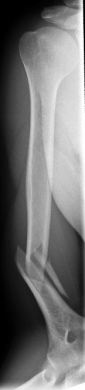

Picture: In the above pictures, a slightly shifted subcapital humeral fracture was internally splinted using intramedullary nail. The left picture is a follow-up examination half a year after the accident and shows the complete healing of the fracture with correct position of the bone.